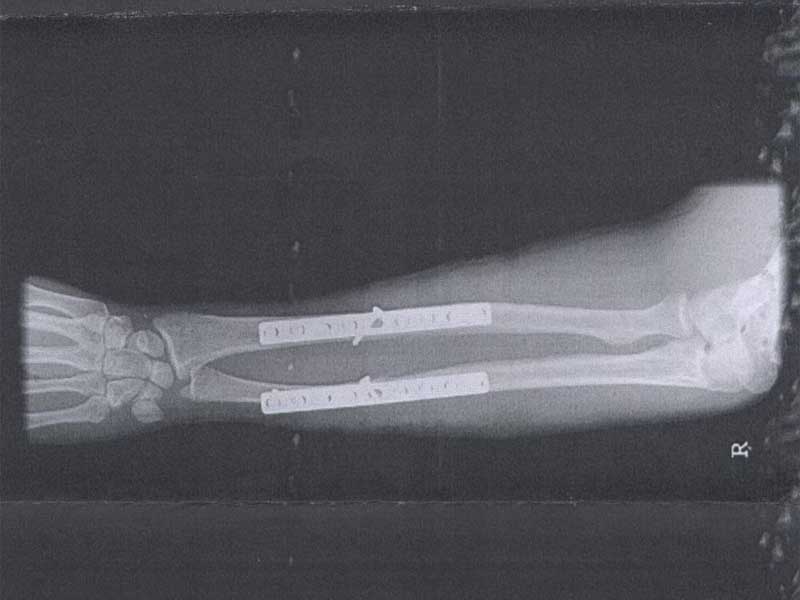

In gedenken An Dark's TDR leidet ist sie unter einem Laster gekommen der beim Abbiegen nicht auf gepasst hat.

Ergebnis: TDR=Totalschaden Dark-Rider=Arm gebrochen (2x9Loch-Platten und 18xSchrauben)